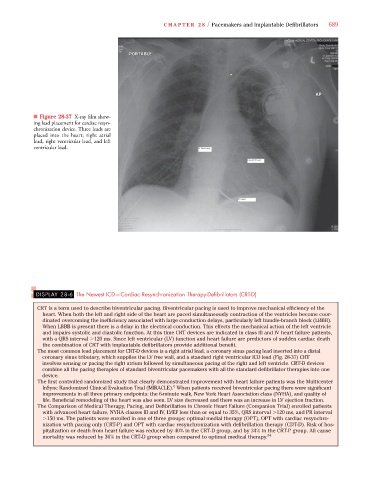

■ Figure 28-37 X-ray film show-

ing lead placement for cardiac resyn-

chronization device. Three leads are

placed into the heart; right atrial

lead, right ventricular lead, and left

ventricular lead.

The most common lead placement for CRT-D devices is a right atrial lead, a coronary sinus pacing lead inserted into a distal

coronary sinus tributary, which supplies the LV free wall, and a standard right ventricular ICD lead (Fig. 28-37) CRT

involves sensing or pacing the right atrium followed by simultaneous pacing of the right and left ventricle. CRT-D devices